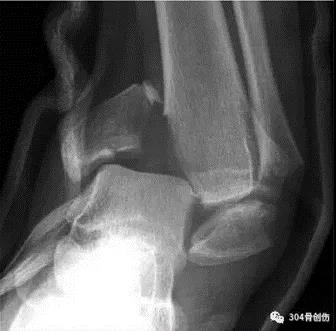

Lauge-Hansen-旋后外旋(SE)损伤时足呈跖屈内收内翻位,距骨外旋(胫骨内旋)。Ⅰ°:距骨外旋使腓骨受到向外、向后的应力,下胫腓前韧带损伤或韧带附着点撕脱性骨折,或者同时又骨间韧带损伤。Ⅱ°:外力继续作用,腓骨继续受到向外、向后的旋转应力,造成腓骨的螺旋性骨折。(特点:腓骨骨折线从后上向前下。并且多位于下胫腓联合部位。)Ⅲ°:外力继续作用,下胫腓联合后韧带紧张,造成下联合后韧带的断裂或后踝的撕脱骨折。Ⅳ:外力还继续,距骨旋转使三角韧带紧张,造成内踝的撕脱性骨折或者是三角韧带的断裂